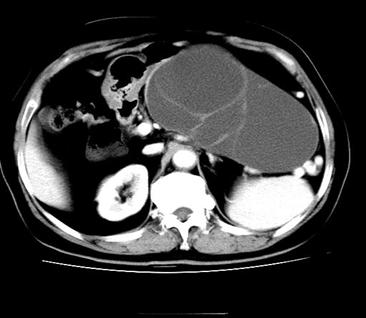

IPMN可以引起胰腺导管的明显扩张

根据世界卫生组织(WHO)1996年公布的诊断标准,IPMN可分为:胰腺管内乳头状粘液性囊腺瘤(IPMA)、胰腺导管内乳头状粘液*交性**界性囊腺瘤(IPMB)、胰腺导管内乳头状粘液性囊腺癌(IPMC),其病情严重程度逐渐上升;根据病灶发病部位的不同,IPMN又可分为:主胰管型——局部或广泛主胰管扩张,扩张导管内可见强化的壁结节,此型恶性可能大,分支型——好发生于胰腺钩突部,表现为分叶状或葡萄串样囊性病变,并与主胰管相通,恶变率较低,以及混合型。